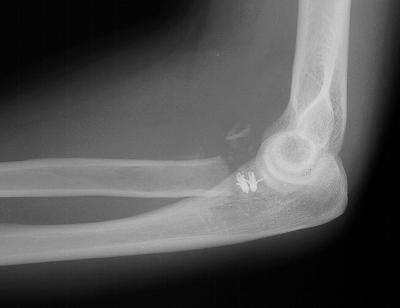

Radial head excision and coronoid soft tissue attachment reinsertion with bone anchors:

Remodelling, heterotopic ossification and posttraumatic joint changes two years postoperative, but no instability: